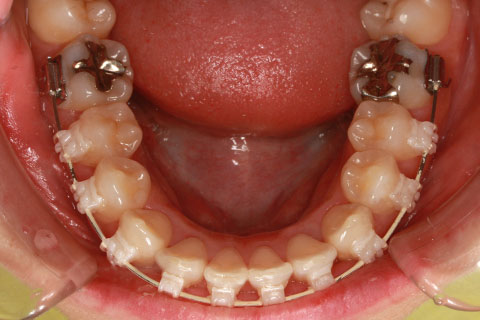

症例

- 年齢・性別

- 30歳女性

- 治療期間

- 3年0ヶ月

- 抜歯

- 上下左右4番抜歯

- 治療費

- 110万円

- 備考

- マルチブラケットを用いた矯正治療

- 治療内容

- 上下顎前突を4本抜歯にて矯正治療

- 施術の副作用(リスク)

- 表側矯正と比較して、歯根の角度を確立する「トルク」の力がかかりにくい。